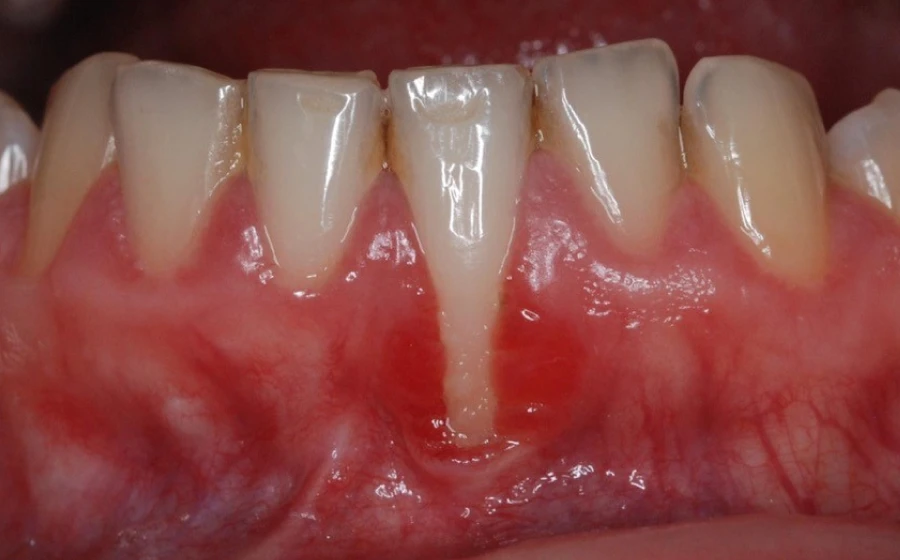

La récession gingivale

La récession gingivale est l’une des principales indications. Elle survient lorsque les gencives se rétractent, exposant les racines des dents. Cela peut être dû à un brossage agressif, à une maladie parodontale ou à un traumatisme. La chirurgie muco-gingivale couvre les racines exposées et renforce les gencives.